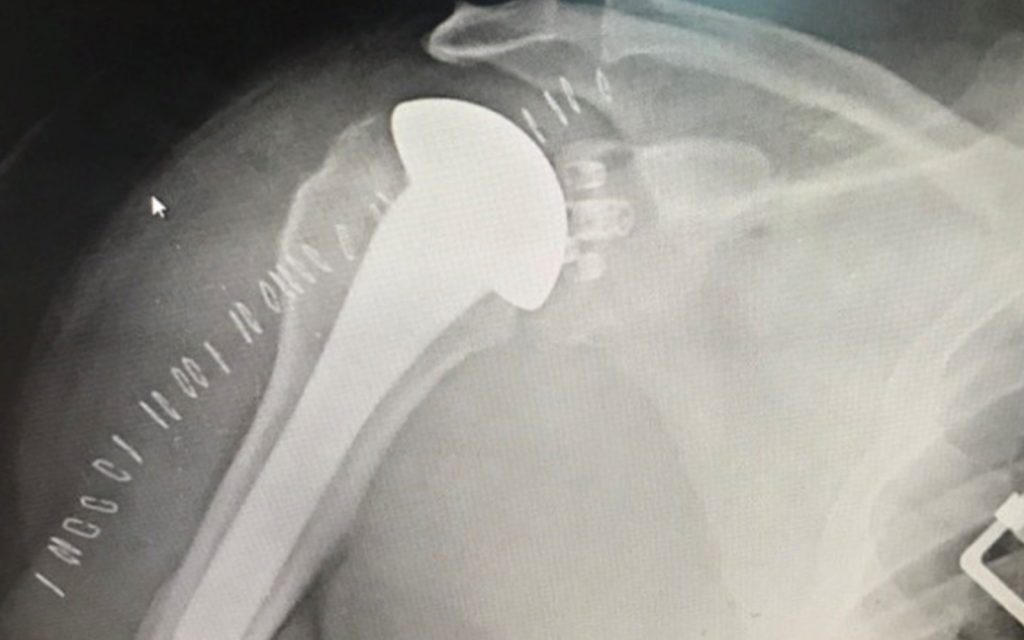

This is a case of a 60-year-old male with a TSA presenting with inability to lift his shoulder two years out of TSA, and rotator cuff failure. In my practice, rotator cuff has been the most common presenting symptom and indication for short term revision shoulder arthroplasty.

Revision to RSA starts with the removal of the humeral head. Next a 360-degree capsular release is performed, and the glenoid component and scar tissue are removed in a systematic manner. Limited reaming and glenoid grafting are performed as needed, to place the reverse shoulder metaglene and screws. The glenosphere is then placed and secured with a locking screw or a morse taper. Attention is then turned toward the placement of the humeral platform tray and reverse polyethylene. The majority of the time there is no need to sink the stem further.